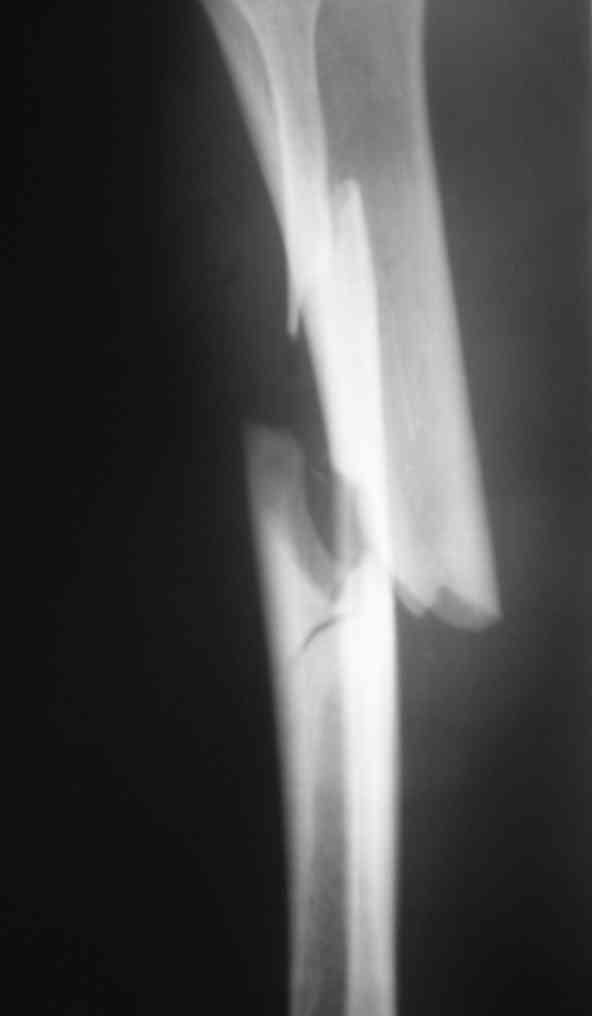

Дорогой Александр. Имею скромный опыт использования системы Fixion при переломах плеча, бедра и тибии. Всего 18 наблюдений с сентября 2006 г. Результаты отличные. Гвоздь индивидуален для каждого медуллярного канала. Легко имплантируется как в узкий, так и в деформированный канал. Это позволяет применять метод интрамедулярного остеосинтеза без ненужных потерь времени операции, флюороскопии и реально снижает крвопотерю и операционный риск. Удаление происходит без проблем. Особенно интересны больные с ипсилатеральными переломами бедра и голени.

В отношении ранней нагрузки при спиральных переломах лучше не торопиться. По данному случаю необходимо достигнуть исчезновения щели между штифтом и внутреним кортексом по Rg. А так картинка прекрасная - и длина сегмента и репозиция. Можно поздравить, коллега!